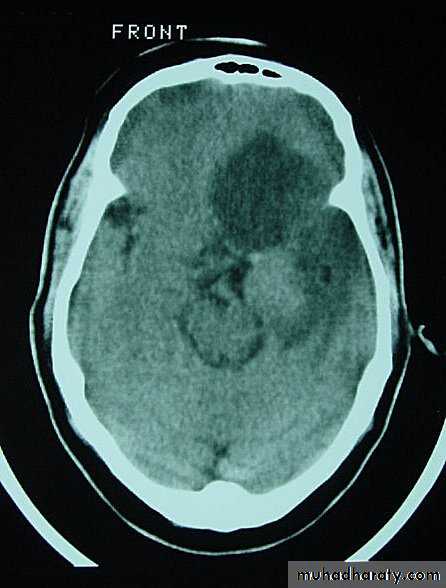

Metastatic Brain Tumours

• Constitute 15% of intracranial tumours.

• The commonest sites of origin are the lung (40%) and breast (10-30%), in addition to melanoma (5-15%), kidney and colon.

• In 15% of cases, a primary source is never found.

• On CT, they only show well with intravenous contrast.

• Steroids may help reduce peritumour oedema.

• Surgery may be appropriate for an isolated metastasis.

CSF shunt used for lesions causing Hydrocephalus.

• Radiotherapy can be used for multiple metastases.